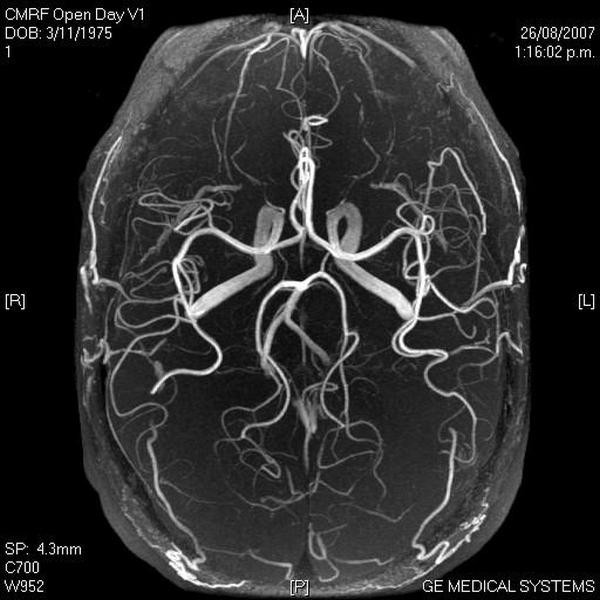

Основными методами диагностики при гипоплазии позвоночных артерий являются УЗИ кровеносных сосудов (допплерография, дуплекс сканирование) и МР — ангиография:

- УЗИ измеряет разницу в скорости кровотока, на основании которой предполагают сужение сосуда.

- МР — ангиография является более точным методом обследования при недоразвитии позвоночной артерии, так как использует магнитный резонанс и позволяет визуализировать дисплазию сосудов. Повышает информативность диагностики введение в вену контрастного вещества.

МРТ-диагностика также рекомендуется при вертеброгенных патологиях позвоночника (шейного, пояснично-крестцового отдела) и спинного мозга, в том числе и при синдроме позвоночной артерии, когда необходимо рассмотреть объекты, сдавливающие ПА.